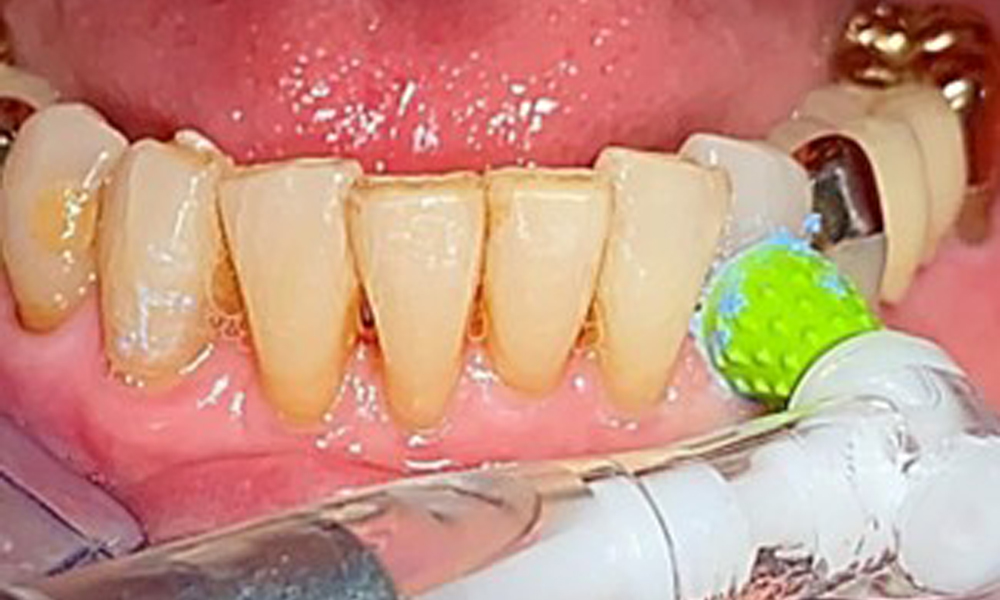

An air polishing system should be used with low-abrasive powder to remove biofilm from the restoration margins, interdental areas and implant surfaces (Fig. 12). Selective polishing (Fig. 13) should be used to smooth any less sensitive areas, as this decreases bacterial reattachment (9).

Air polishing (Proxeo Aura, W&H, shown here) of an implant.

Fig. 12: Air polishing (Proxeo Aura, W&H, shown here) of an implant.